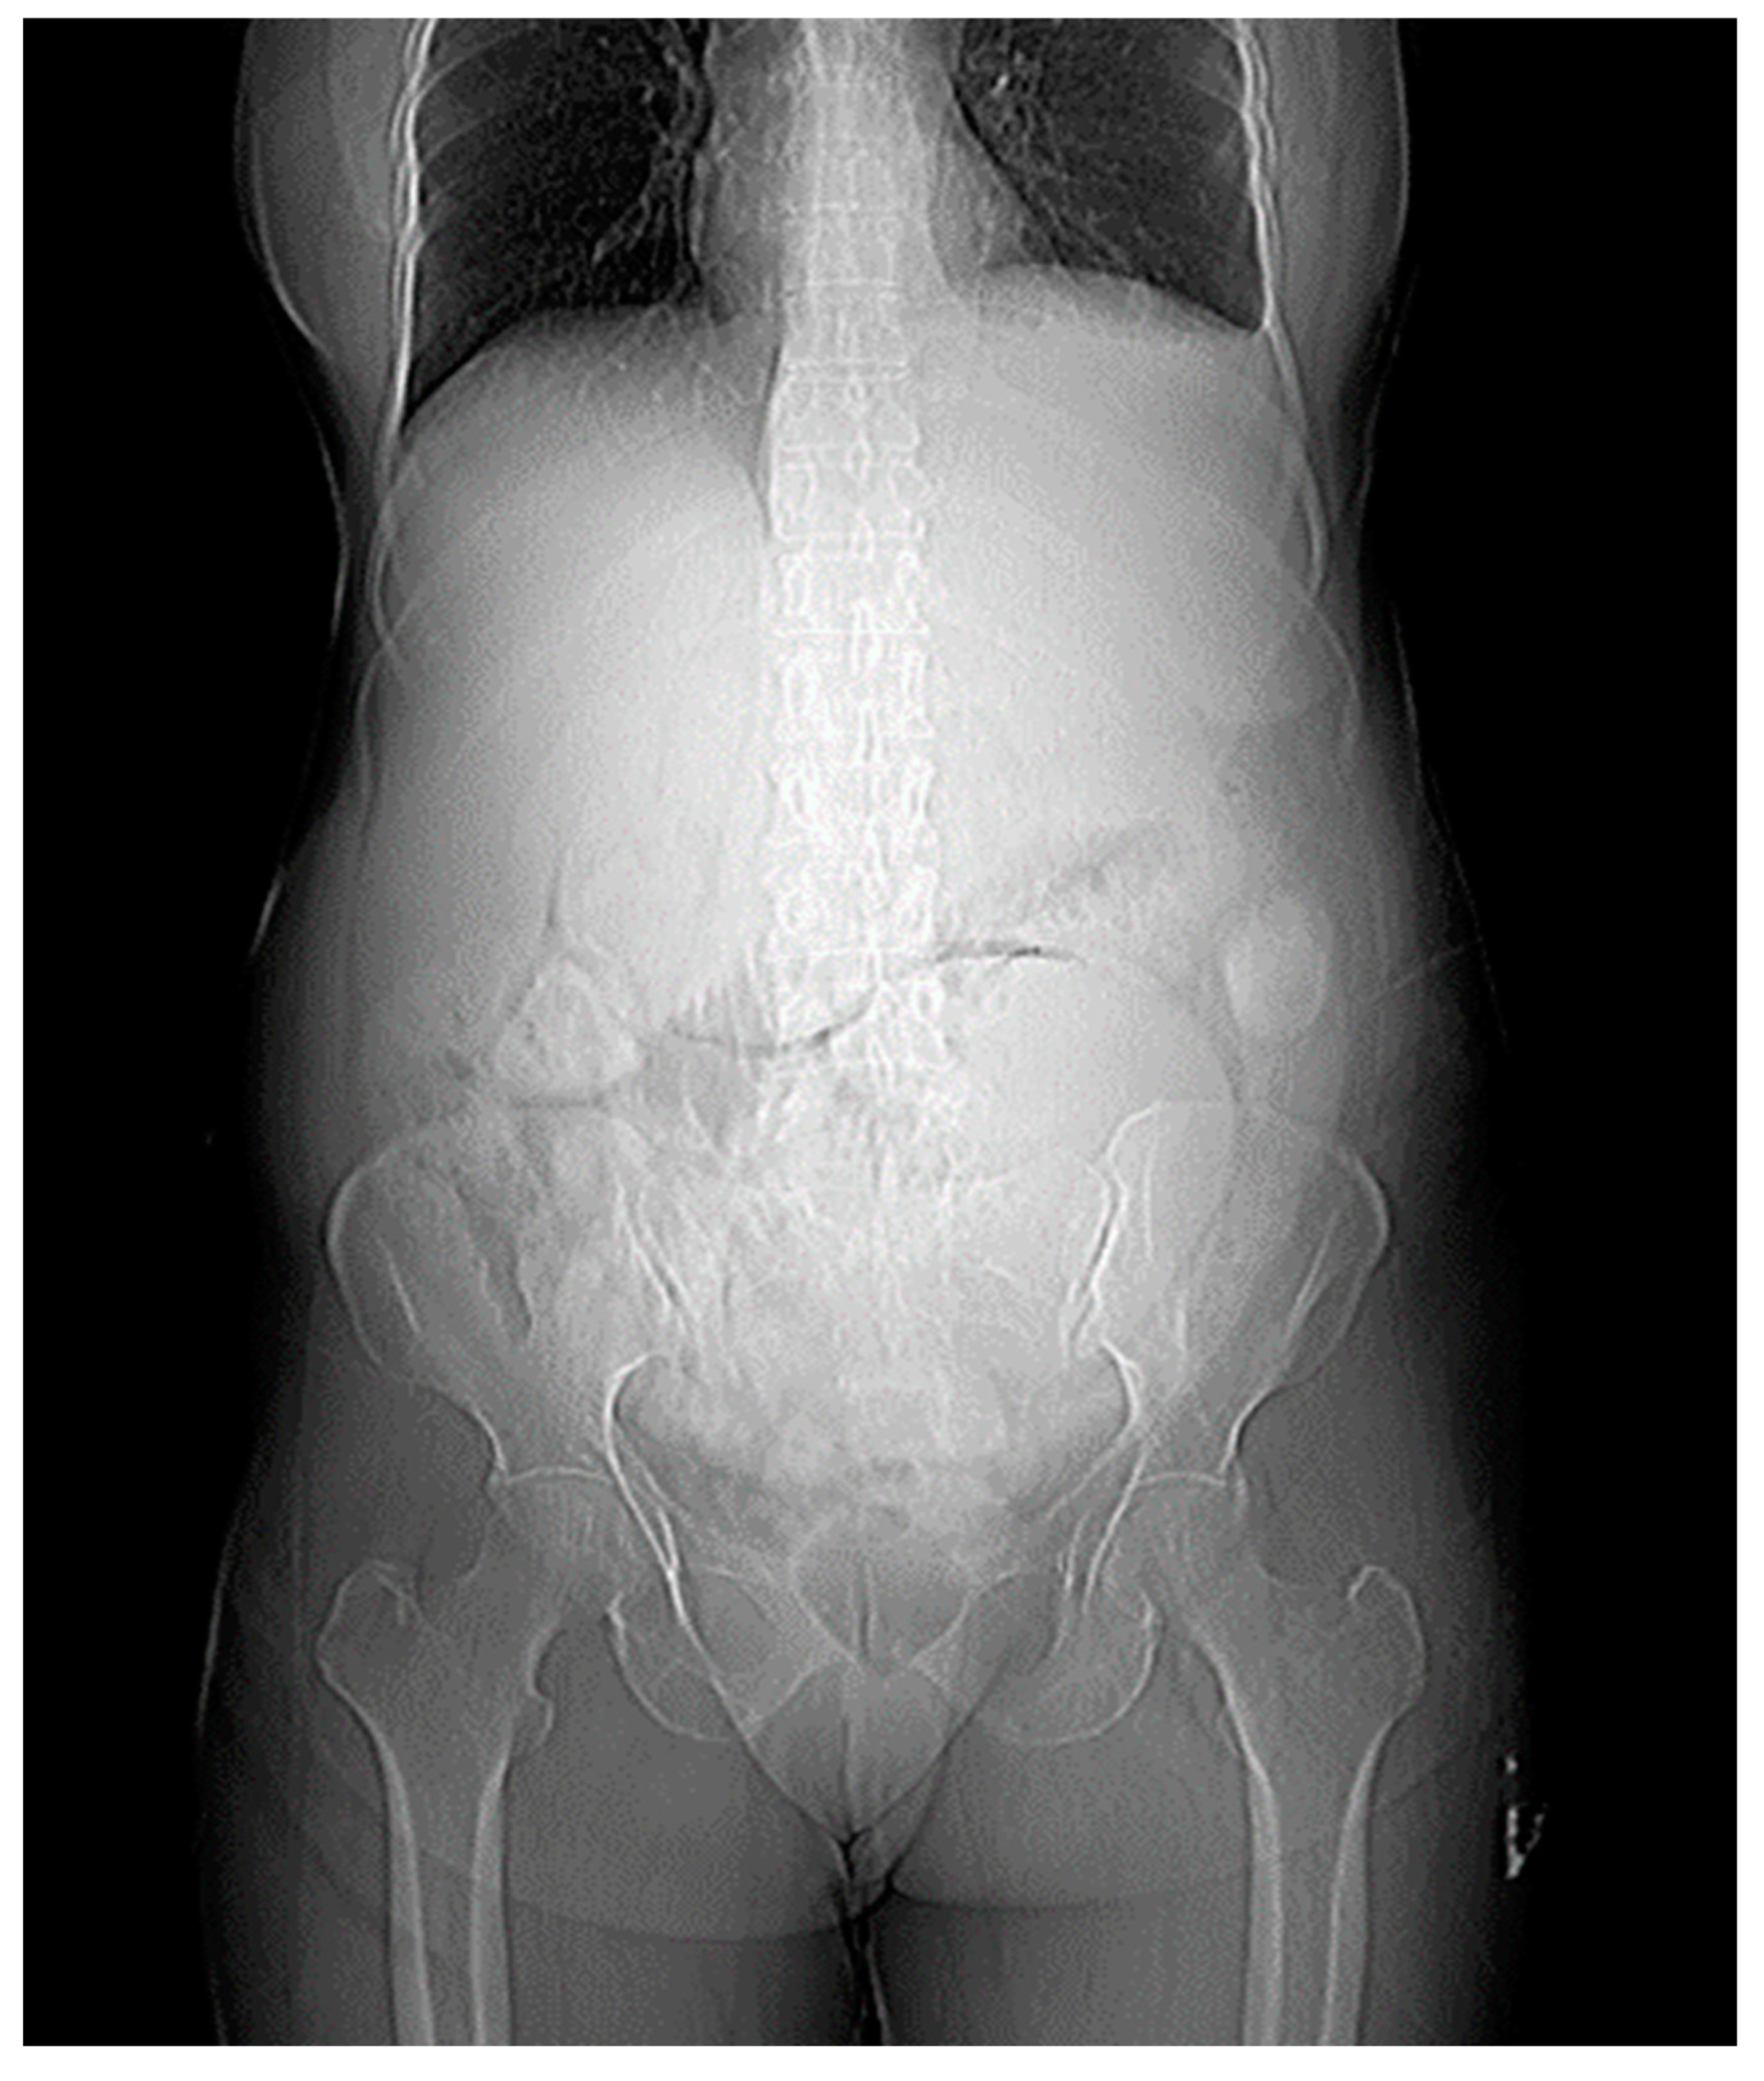

X-ray Findings

The X-ray findings reveal several significant observations. Firstly, there is a large soft tissue opacity observed in the epigastric, left hypochondriac, and left lumbar regions, causing displacement of the bowel loops in a peripheral manner. This particular opacity appears to be extensive, covering multiple abdominal regions.

Secondly, another soft tissue opacity is identified in the left iliac fossa, hypogastrium, and pelvis. The presence of this opacity in the lower left quadrant of the abdomen suggests potential implications for the structures in this area.

Furthermore, an enlargement of the hepatic shadow is noted in the X-ray images. This finding indicates an increase in the size of the liver, which may warrant further investigation into potential underlying causes.

Lastly, the X-ray reveals blunting of the left costophrenic (CP) angle. This observation suggests a reduction in the sharpness of the angle formed by the diaphragm and the ribcage on the left side, and it could be indicative of certain pathological conditions.